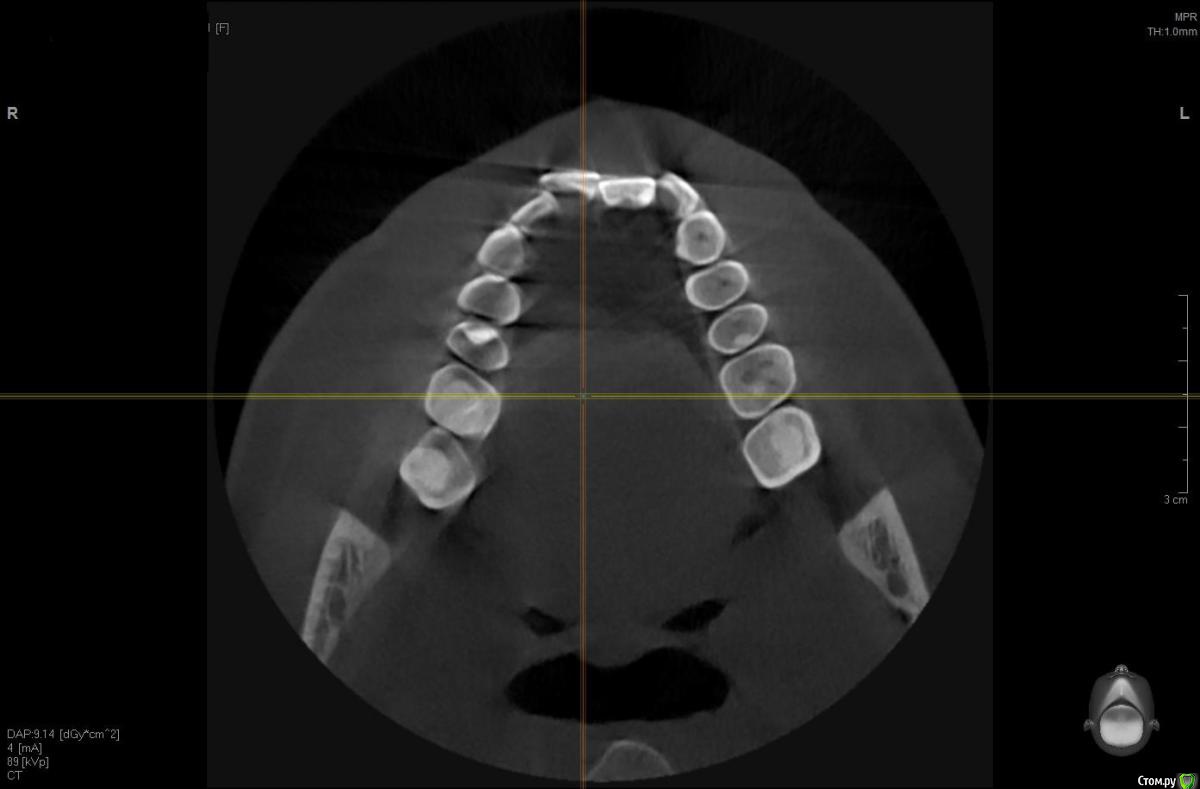

Brigita Опубликовано 3 апреля, 2017 Поделиться Опубликовано 3 апреля, 2017 Смысл невелик - Небольшое расширение на зубоальвеолярном уровне. Но проверить надо, есть ли куда расширятся- это можно на кт сделать. 1 Ссылка на комментарий

solitary Опубликовано 3 апреля, 2017 Автор Поделиться Опубликовано 3 апреля, 2017 Brigita, огромное вам спасибо, что находите время отвечать на мои вопросы http://i12.pixs.ru/storage/3/3/1/1jpg_6052132_25752331.jpgКТ у меня есть, сделанная в рентгенодиагностическом центре Пикассо. Если потребуется, я могу выслать. Сделал скриншот ВЧ, но наверное неправильно выставил оси в программе. Посмотрите пожалуйста. Ссылка на комментарий